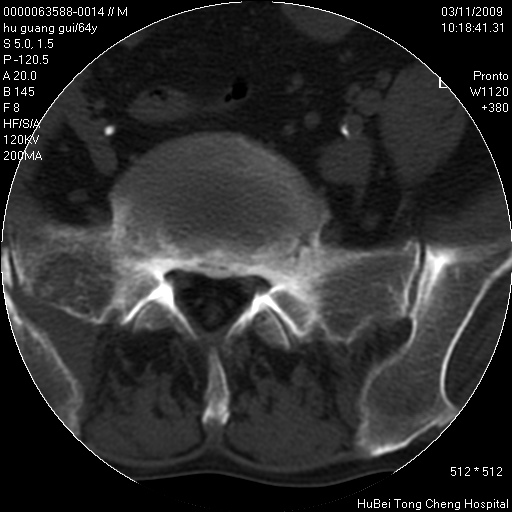

患者 男,64岁。腰痛十余天。(临床未提供其他病史)

临床诊断:腰痛原因待查(腰椎间盘突出症?)。

腰椎间盘ct轴位平扫(层厚5mm,层距4mm),图像如下:

腰椎退行性变,腰4—5椎间盘膨出。

右侧骶骨侧块骨侵蚀,骶髂关节骨性关节面破坏,并见软组织肿块,考虑骨转移瘤可能,进一步检查。

1.腰椎退行性变,腰4—5椎间盘膨出。

2.右侧骶骨侧块骨侵蚀,骶髂关节骨性关节面破坏,并见软组织肿块,考虑:脊索瘤,骨转移瘤可能,进一步检查。

1)腰椎退行性变,l4—5椎间盘膨出。2)骶骨右侧块骨转移瘤可能,3)水平骶椎。建议作一步检查。